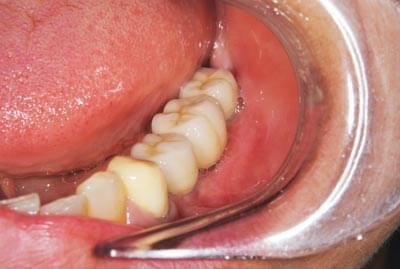

写真は、抜歯後の口腔内の写真です。見るからに、骨が少なく、陥凹してしまっていました。